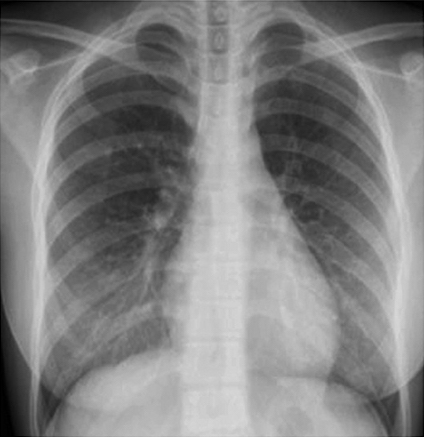

Figure 6 presents image examples for each class retrieved from the RYDLS-20 database. It is worth to mentioning that we have no further information concerning the CXR images with regarding the CXR machine used to take the image, as well as the origin, age and ethnicity of the people whose these images belong to.

Refer to caption

(a) Normal.

(b) COVID-19.

(c) SARS.

(d) MERS.

(e) Pneumocystis.

(f) Streptococcus.

(g) Varicella.

Figure 6: RYDLS-20 image samples.